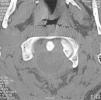

Mujer de 16 años con historia por tortícolis fija aparecida tras cirugía tiroidea; tratada mediante AINE y ortesis cervical blanda, no mejora por lo que a las 10 semanas es enviada a nuestro centro. El diagnóstico, SRCAA tipo I de Fielding, se obtuvo mediante TAC (fig. 6A) con reconstrucción tridimensional (fig. 6B) utilizándose el mismo protocolo de tratamiento que en los otros pacientes, llegando a 14 kg; a las 3 semanas la movilidad era simétrica y la TAC confirmó la reducción completa de la divergencia rotacional (fig. 7), inmovilizándose con halo-yeso 6 semanas y ortesis cervical blanda otras 6 semanas. Dos años después, la función es completamente normal, no habiendo presentado episodios de cervicalgia ni tortícolis.

Figura 6. A: tomografía axial computarizada convencional en la que se puede apreciar la rotación de 32° entre C1-C2 en el paciente n.O 3. B: la reconstrucción tridimensional nos muestra la deformidad típica de rotación y pinzamiento C1-C2.

El diagnóstico radiológico es difícil, ya que la deformidad y el dolor impiden obtener buenas proyecciones, así en la radiografía anteroposterior simple se superpone la cabeza, y en la lateral se puede observar una falta de paralelismo entre el cráneo y la columna; la radiografía transoral de odontoides puede ser de gran valor, mostrando una asimetría entre el diente del axis y las masas laterales del atlas con posible pinzamiento de las facetas8. Se ha sugerido la utilización de la TAC dinámica, con rotación a izquierda y derecha de la cabeza, pero en situación de SRCAA la movilización es dolorosa, por lo que difícilmente se obtendrá la cooperación del paciente, pudiendo llevar a confusión en el diagnóstico13. En una tortícolis aguda no parece estar indicado el estudio con TAC14,15, pero en casos persistentes con sospecha de SRCAA es muy útil para confirmar el diagnóstico, ya que mostrará la divergencia rotacional C1-C2 que se puede cuantificar midiendo la angulación existente entre las líneas que unen las apófisis transversas del atlas y del axis (fig. 2)16. En la TAC tridimensional se puede apreciar la deformidad rotacional con el desplazamiento completo de las facetas articulares, la situación asimétrica de la odontoides en el arco anterior del atlas --que asimismo puede orientar sobre la integridad del ligamento transverso-- y el desplazamiento de la espinosa de C24. La RMN es un buen complemento, ya que puede informar de interposición de partes blandas7, así como de la posible lesión del ligamento transverso17, por lo que en caso de duda puede indicar la necesidad de estabilización quirúrgica. En nuestra serie, ante una sospecha de SRCAA, se utilizó la TAC simple como método diagnóstico (fig. 2 y 4A), completándose en el tercer caso con reconstrucción tridimensional (fig. 4B) en la cual fueron muy evidentes las alteraciones torsionales del complejo atlantoaxial.